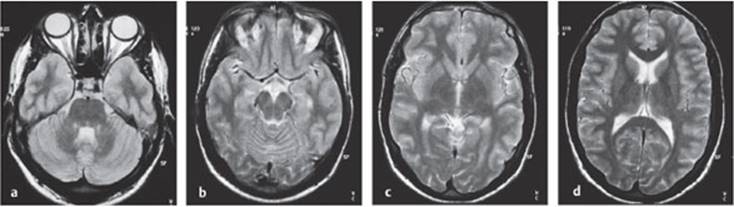

Technique. Single photon emission computed tomography uses either a 99m-technetium compound or 133I-am-phetamine as a tracer. The purpose of this type of study is to measure regional cerebral blood flow.

Indications. SPECT can be performed to demonstrate reduced perfusion of the brain, e.g., in stroke or in Alzheimer disease, which is associated with reduced activity in the temporoparietal region (Fig. 4.13a, b). It can also be used to detect focal pathological processes of other kinds, e.g., epileptogenic foci (Fig.4.13c).